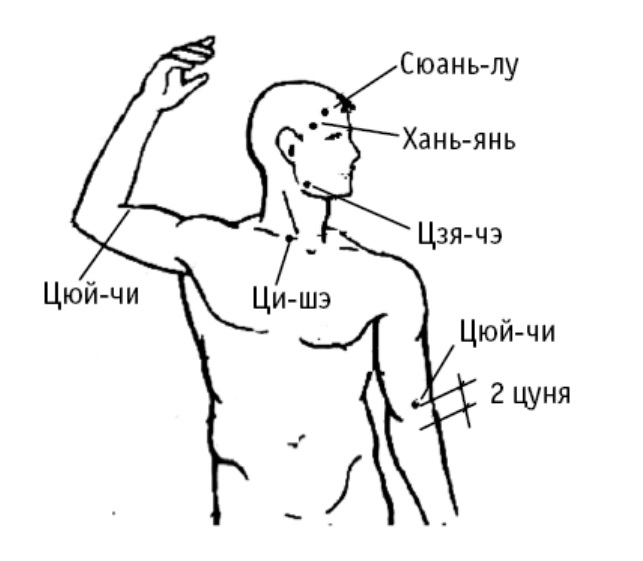

Сюань-лу («подвешена на черепе») расположена на виске, на 2 цуня выше уха по ходу роста волос.

Используется при лечении головной боли, боли в наружном углу глаза, отеках лица, лихорадке, зубной боли, при повышении давления.

Хань-янь («трясти головой» и «унять (тряску)») расположена на виске, на 1 цунь ниже Сюань-лу по ходу роста волос.

Используется при головной боли, головокружении, судорогах, шуме в ушах, снижении остроты зрения.

Цзя-чэ («повозка щеки») расположена в углу нижней челюсти. При сомкнутых челюстях в этой точке можно нащупать выпуклые жевательные мышцы, когда рот раскрыт – в месте расположения точки нащупывается впадинка.

Точка используется для лечения головной боли и боли в шее, уменьшения боли и напряжения в затылочных мышцах, для лечения зубной боли и болей в области челюсти.

Ци-шэ («жилище энергии») расположена над верхним краем ключицы, между грудинной и ключичной головками грудино-ключично-сосцевидных мышц.

Воздействие на ци-шэ благотворно также при кашле, боли и отечности в области горла.

Цюй-чи («изгиб озера») находится на наружной стороне плеча. Ее находят при согнутом локтевом суставе в углублении локтевой складки.

Точку используют для снятия головной боли, уменьшения зубной боли, нормализации артериального давления при гипертонии.

Дополнительный эффект от акупрессуры точки цюй-чи: лечение локтевого сустава и предплечья, уменьшение болей в спине; лечение кашля, уменьшение отеков слизистой оболочки носоглотки; облегчение лихорадочных состояний.